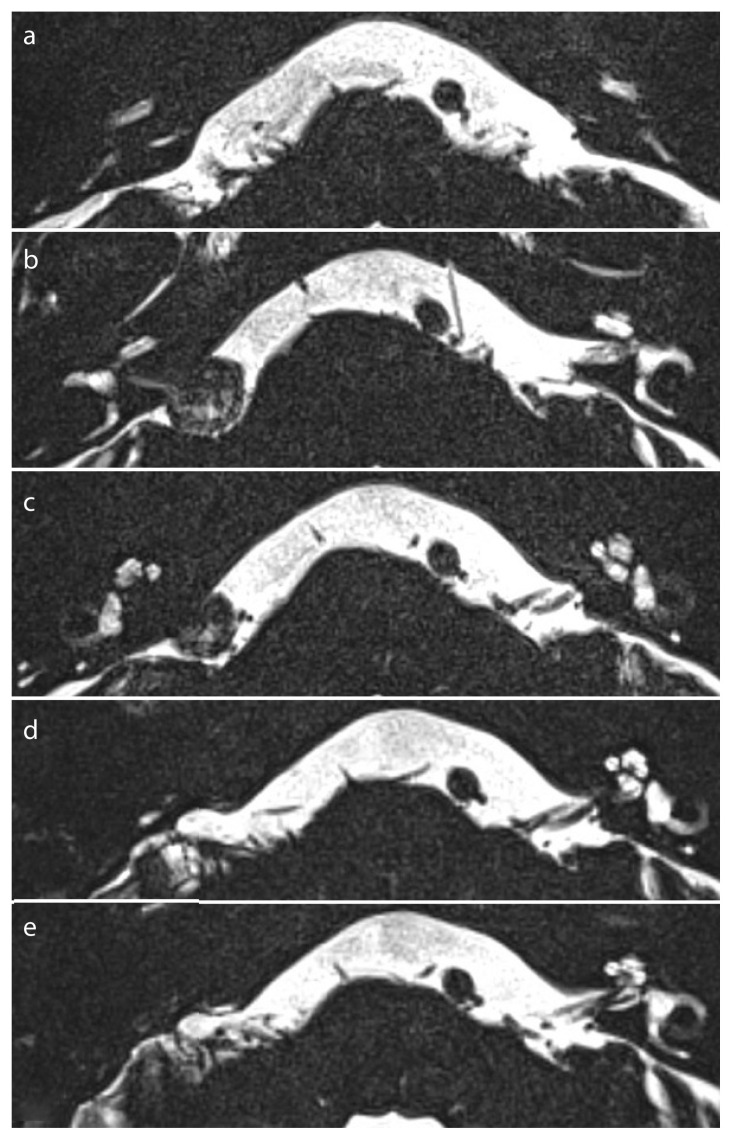

Figure 2. a–e.

Imaging before and after surgery via a translabyrinthine approach for a right-sided VS. a) Preoperative patency in the basal turn; b, c) Preoperative patency in the apical turns; d) Postoperative partial obliteration in the basal turn; e) Postoperative complete obliteration in the apical turns.